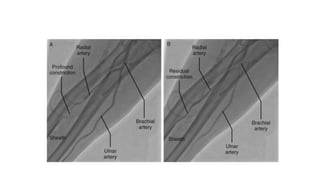

CORONARY ANGIOGRAPHY

โ€ข Gold standard for diagnosis of CAD

โ€ข Through femoral or radial arteries

โ€ข Passage of special catheters retrograde into aortic root,

cannulation of the left and right coronanry arteries

โ€ข Injection of a radioopaque agent to replace blood

โ€ข Xray taken to see the arteries in different views